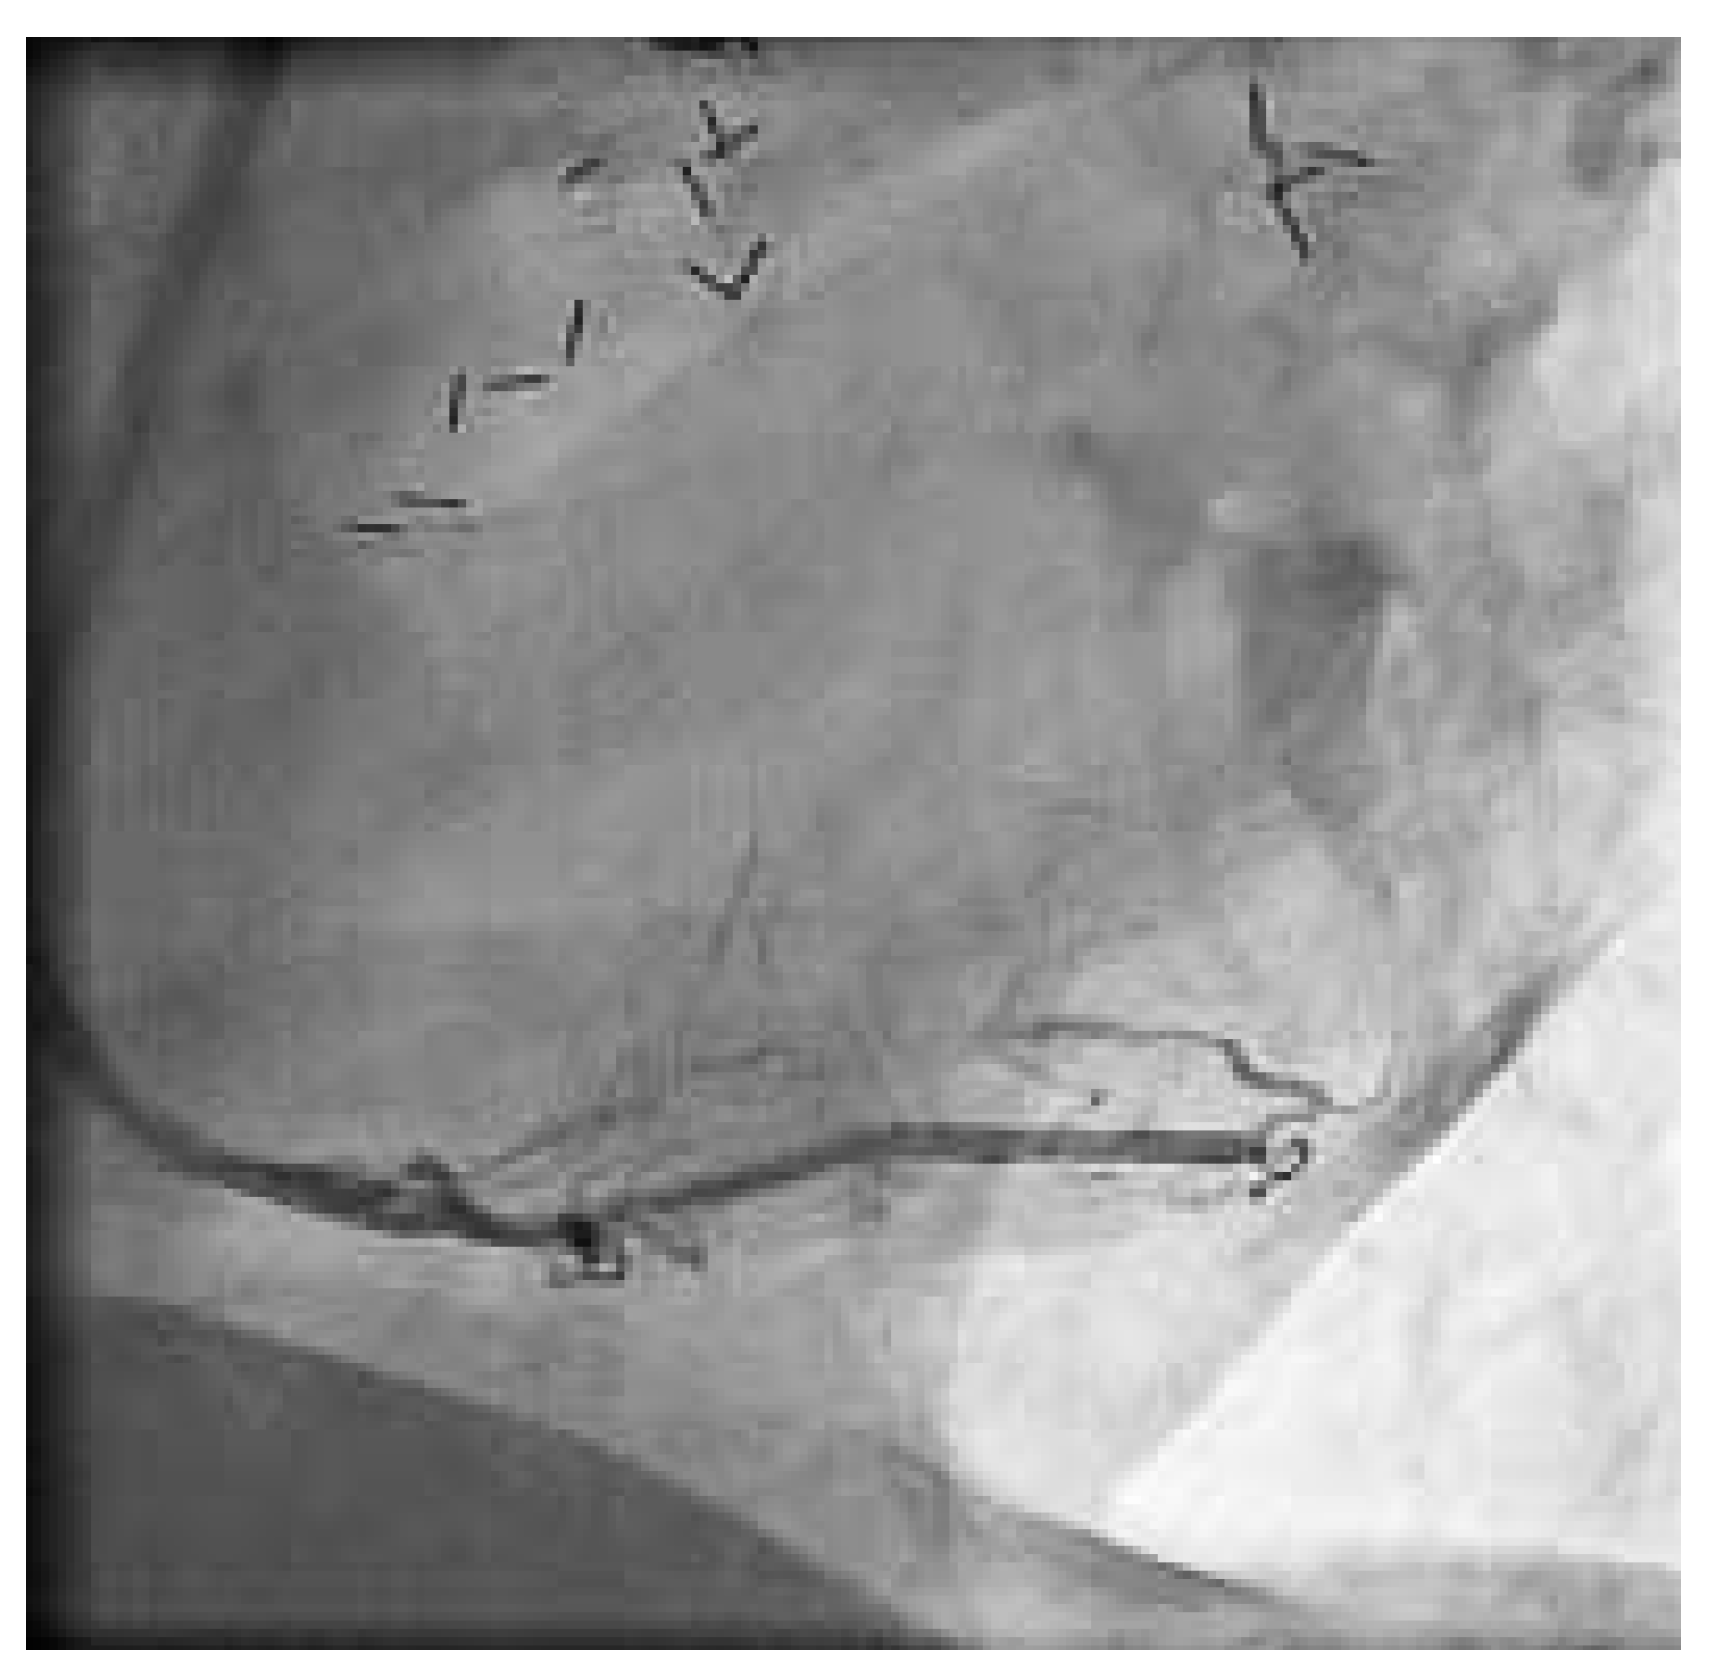

Abbildung 3. Einlage zweier langer beschichteter Stents bis über dem mittleren Gefässdrittel, wobei die Kontrastmittelsäule immer noch im proximalen Gefässanteil still steht.

Der 74jährige Patient wurde 1991 chirurgisch revaskularisiert (LIMA zu Diagonal-Ast und RIVA, Venengraft zum Ramus intermedius und Posterolateral-Ast [PLA]. 1999 wurde eine perkutane Intervention am RCAmit Stent-Einlage vorgenommen. Zwei Jahre später wurde der Venengraft mit einem Stent versorgt und der RCA rekanalisiert, erneut dilatiert und eine Brachytherapie appliziert. Im Herbst 2003 begann der Patient erneut über typische und reproduzierbare Präkordialgien, entsprechend einer CCS-Klasse III, zu berichten. Eine Rekoronarangiographie zeigte weiterhin einwandfreie Verhältnisse des LIMA- und des gestenteten Venengraftes, die RCA war jedoch am Abgang langstreckig verschlossen (Abb. 2). Der Herzchirurg war der Meinung, dass eine erneute perkutane einer chirurgischen Revaskularisation vorerst vorzuziehen wäre. Eine intravenöse Abciximab-Gabe wurde begonnen. Nach schrittweiser Drahtpassage, alternierend mit repetitiver Ballondilatation bis über die Bifurkation, intrakoronarer Nitrat-Gabe und Einlage zweier langer beschichteter Stents bis über dem mittleren Gefässdrittel, stand die Kontrastmittelsäule immer noch im proximalen Gefässanteil still (Abb. 3). Wir entschieden uns zur Verwendung des «Export»-Thrombus-Aspirationskatheters. Erst nach mehreren Durchgängen mit dem Aspirationskatheter, bei denen thrombotische Debris aspiriert wurden, kam das grosse Gefäss zur Darstellung und wurde der Fluss wieder hergestellt. Das angiographische Resultat war nach Vervollständigung der Intervention sehr zufriedenstellend (Abb. 4). Der Patient war nach der Intervention während 8 Monaten beschwerdefrei und leistungsfähig. Aufgrund eines Prostatakarzinoms wurden mehrere urologische Eingriffe und eine lokale Bestrahlungstherapie notwendig, weshalb Clopidogrel und die orale Antikoagulation sistiert werden mussten. Die perioperative Periode verlief ohne kardiale Komplikationen, der Patient jedoch wurde wieder symptomatisch (CCS-Klasse II). Nicht zuletzt, weil nun wahrscheinlich eine chirurgische Revaskularisation nicht mehr zu umgehen ist, kann sich der Patient zurzeit noch nicht zur diagnostischen Koronarangiographie entschliessen.